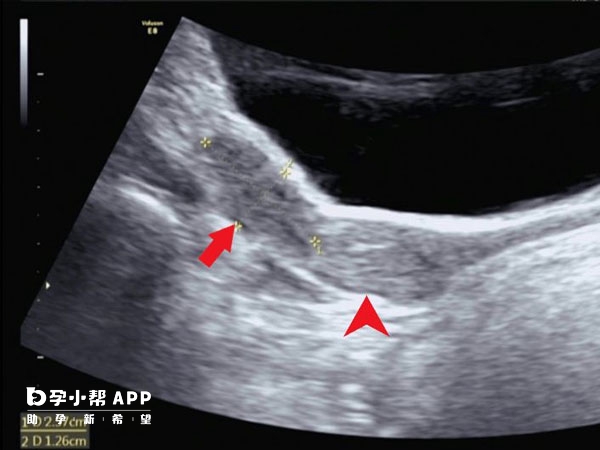

幼稚子宫结构和形状大致正常,但是体积比正常子宫小,而且宫颈相对较长。同时,宫颈外口小,颈管呈圆锥形。幼稚子宫的症状体现在少女月经初潮延迟或者月经稀少,有痛经,甚至闭经。